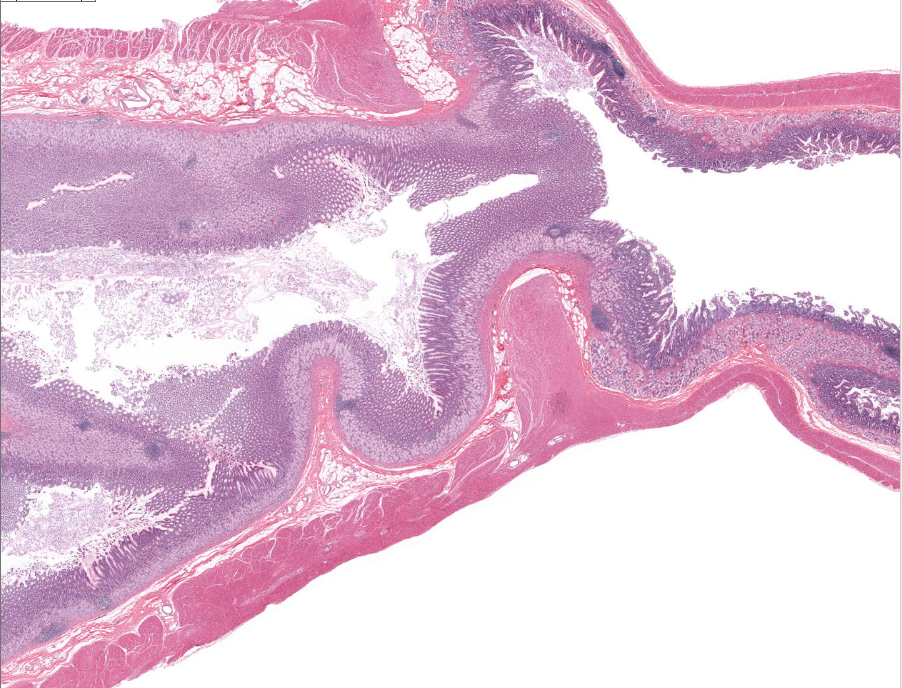

epiglottis

tissue type

strat. squamous non-keratinized epi

found on anterior/lingual surface of epiglottis

(tissue type)

respiratory epi

aka ciliated pseudostratified epithelium

found on posterior/trachea side of the epiglottis

lamina propria of the epiglottis

supports epithelium